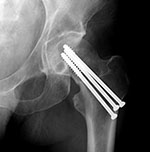

Cannulated screws have a hollow shank, which

allows them to be placed more exactly over a

guide pin (figure: cannulated screw). They are commonly used for fixation

of subcapital hip fractures and may be inserted

percutaneously with fluoroscopic guidance (figure: hip cannulated screws). This surgery is commonly performed by

using a fracture table to provide traction and

maintain reduction during the fixation (Ruedi, 2007; Benjamin, 1994; Berquist, 1995; Freiberg, 2001; Hunter, 2001).

Hip cannulated cancellous fixation screws |

|